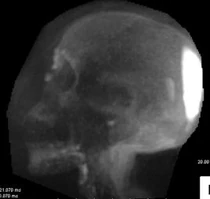

The mummy's body showed signs of Hand-Schuller-Christian disease, typified when a type of immune cell start to multiply rapidly and replace bone and other soft tissues. This left lesions on the skull and spine. Along with the painful lesions, the man also likely suffered from diabetes. There is evidence of the pituitary gland being damaged. This is the third body found with evidence of Hand-Schuller-Christian disease..